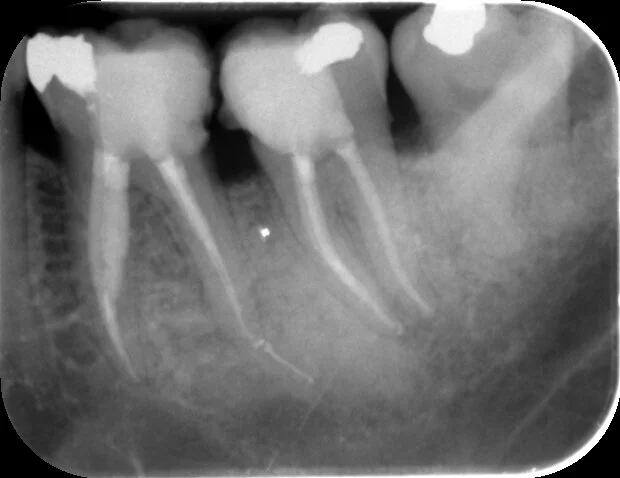

A separated instrument in a mesial canal of the LR6 threatened to compromise successful treatment. The instrument was removed with the help of ultrasonic tips.

A separated file can be seen in one of the mesial canals (turned out to be the mesio-lingual canal), luckily it was visible with the use of high magnification and illumination

The offending instrument